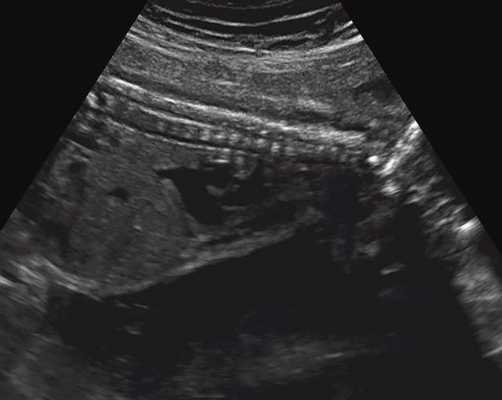

б) Узкая грудная клетка.

в) Узкая грудная клетка.

| Набл. 1. 24,3 нед. | БПР - 25,3 нед. ОГ - 24,6 нед. Аномально повышенная бороздчатость и выпуклость извилин нижнемедиальной поверхности височных долей (рис. 1а). | Торакоабдоминальное соотношение - 66,7% (рис. 1б) Длина ребра - среднее для 16 нед. | Бедренная кость 19,6 мм (47,8% от должной), изогнута ("телефонная трубка") (рис. 1в). Остальные кости - среднее для 15 нед. | Уплощенные тела поясничных позвонков. |

| Набл. 2. 20,3 нед. | БПР - 21,5 нед. ОГ - 20,3 нед. Уплощенный затылок. Выпуклые темпоральные бугры (рис. 2а). Аномально повышенная бороздчатость и выпуклость извилин нижнемедиальной поверхности височных долей (рис. 2б). | Торакоабдоминальное соотношение - 63,3% (рис. 2в) Окружность груди - среднее для 18 нед. Длина ребра - среднее для 15 нед. | Бедренная кость 17,7% (61% от должной), изогнута ("телефонная трубка") (рис. 2г). Остальные кости - среднее для 13-14 нед. | Гипоплазия костей носа. |

| Набл. 3. 24 нед. | БПР - 30 нед. ОГ - 27,2 нед. Уплощенный затылок. Выпуклые темпоральные бугры (рис. 3а). Аномально повышенная бороздчатость и выпуклость извилин нижнемедиальной поверхности височных долей (рис. 3б). | Торакоабдоминальное соотношение - 56,6% (рис. 3в) Окружность груди - среднее для 20 нед. Сердце/грудь (см 2 ) - индекс 0,6. | Бедренная кость 23,1 мм (57% от должной), изогнута ("телефонная трубка") (рис. 3г) Остальные кости - 50% для 15-16 нед. Нормальная установка пальцев кисти (рис. 3д). | Многоводие. |

УЗИ позволяет выделить группу скелетных дисплазий плода с сужением грудной клетки, являющимся одним из важных прогностически неблагоприятных признаков независимо от нозологической формы остеохондроплазий. Во всех представленных нами случаях у плодов отмечены микромелия и гипоплазия грудной клетки (окружность грудной клетки была менее 5% для гестационного срока, а торакоабдоминальное соотношение было в пределах 56,6-67,6%).